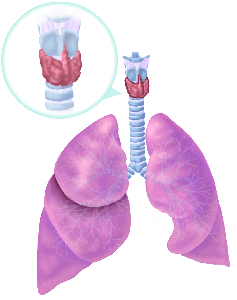

Über 860 Stichworte mit 120 Illustrationen auf 400 Seiten machen aus dem Lexikon der Lunge ein

wertvolles Werk.

Detailreiche Fotografien aus der medizinischen Praxis ergänzen die Texte; moderne, genaue,

wissenschaftliche Zeichnungen geben Einblick in die Anatomie und die Funktion der Lunge und

anderer Organe.